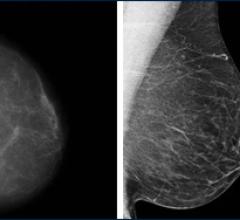

Despite decades of progress in breast imaging, one challenge continues to test even the most skilled radiologists ...

April 7, 2010 - A dual-modality tomographic (DMT) breast scanner, developed by researchers at the University of Virginia Health System (UVA), in a pilot study pinpointed to a much finer degree than mammography, ultrasound, MRI and even a needle biopsy, the location of breast masses and more accurately distinguished between cancerous and harmless lesions.